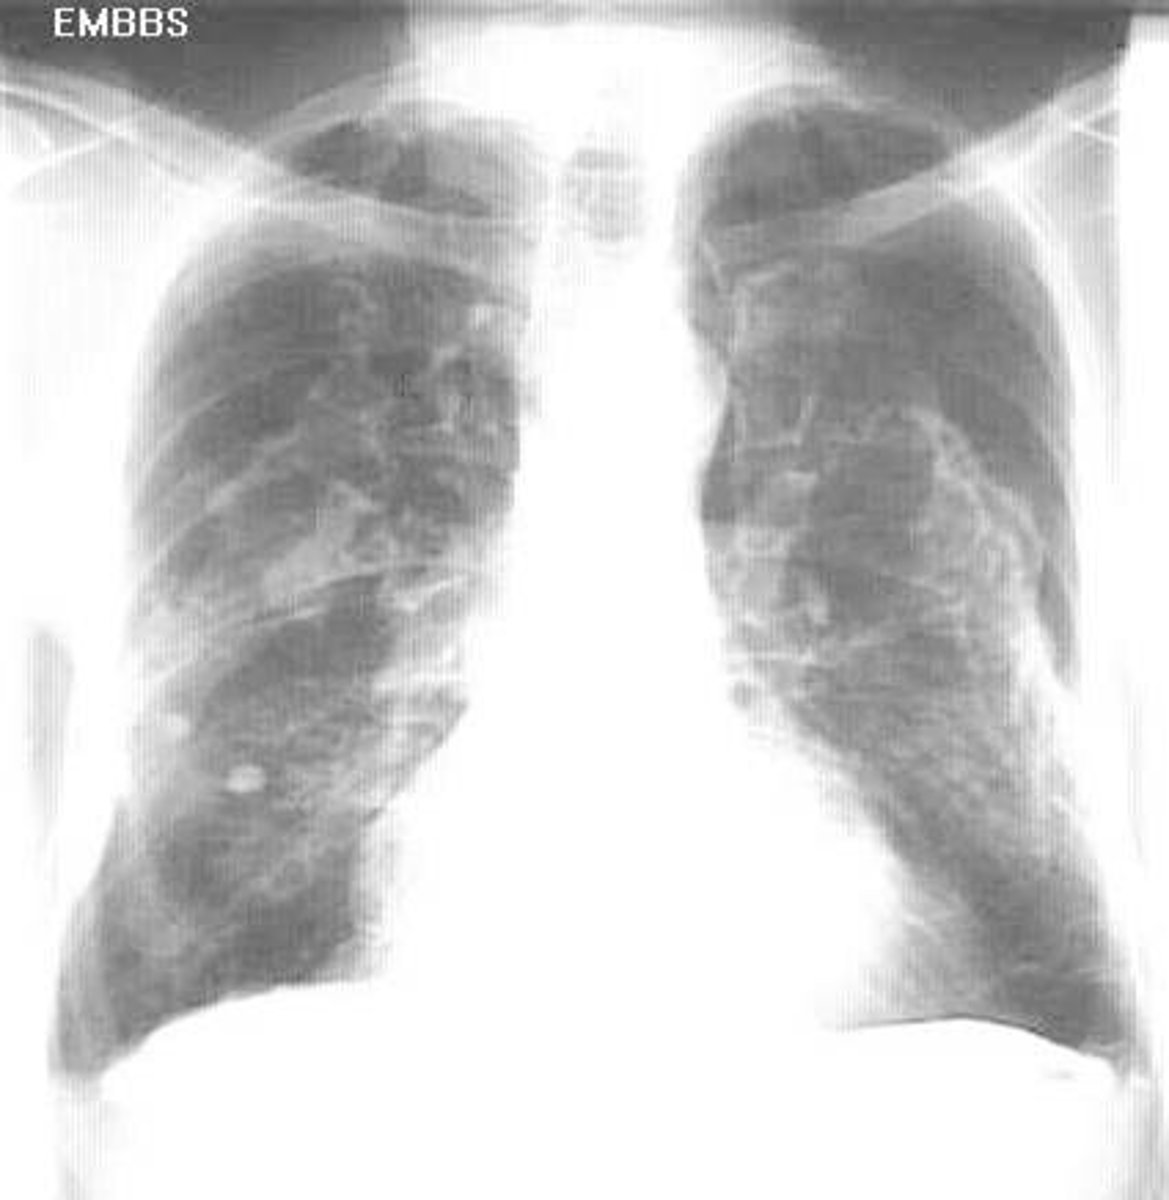

SARS

severe acute respiratory syndrome